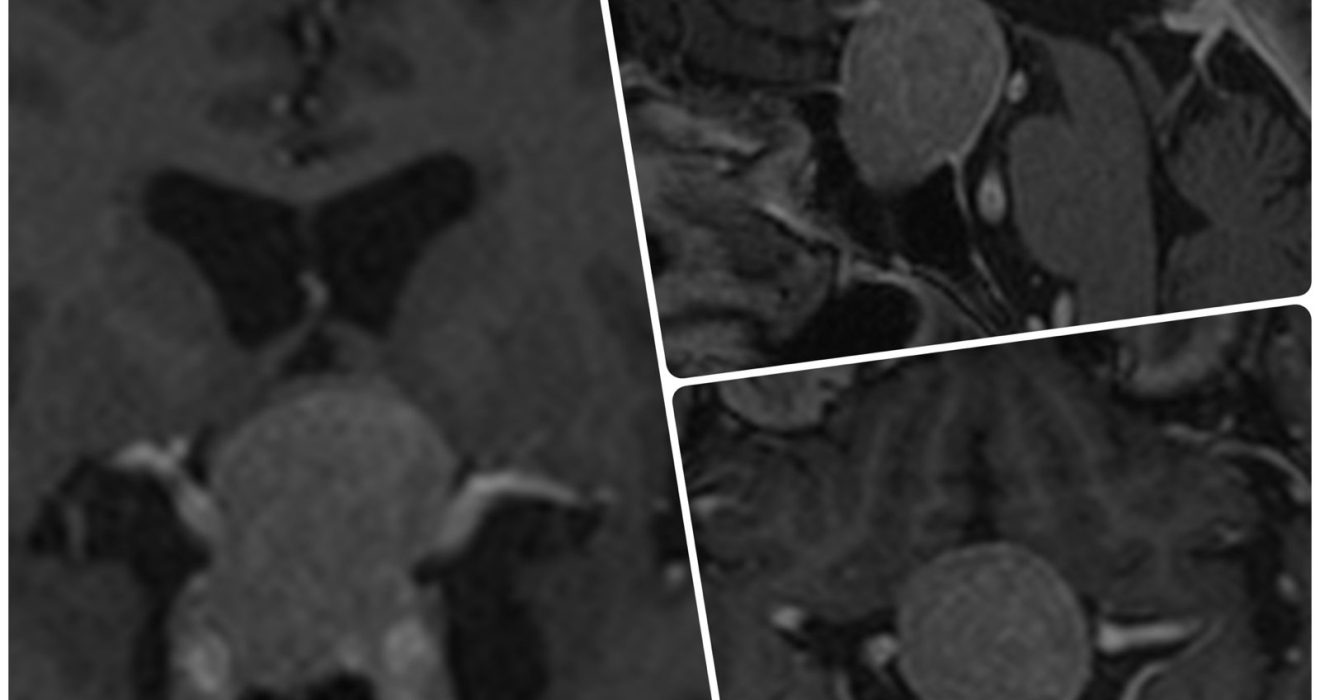

Adenomas de hipófisis: síntomas, diagnóstico y la cirugía que puede devolverte la salud

Los adenomas de hipófisis son tumores benignos que se forman en la glándula pituitaria, una pequeña pero fundamental estructura ubicada en la base del cerebro. A pesar de su tamaño reducido, la hipófisis controla gran parte del equilibrio hormonal del organismo, regulando funciones tan importantes como el metabolismo, el crecimiento, [...]